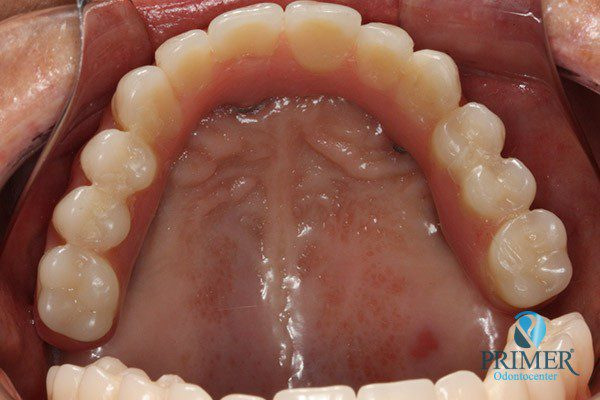

- Depois

- Sorriso final